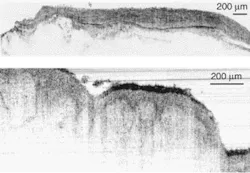

Recently, Wolfgang Drexler and his colleagues at the University of Vienna (Vienna, Austria), along with researchers from MenloSystems (Martinsried, Germany), have tested a broad-spectrum fiber laser emitting at 1375 nm to achieve sub-2-µm-axial-resolution OCT in nontransparent biological tissues.1 This resolution represents a 25% increase in axial OCT resolution. The tissues were ex vivo samples from a human artery and skin, which were imaged through thin layers of water to prevent dehydration and to optimize the index matching (see Fig. 1).

Individual layers and membranes are clearly visible in the artery and skin samples. The researchers believe this shows that an OCT system based on such a stable, low-cost, compact fiber laser has great potential for in vivo OCT clinical studies. To reach this point, laser performance must be improved by smoothing the emission spectrum and increasing the system output power two- to fivefold. A fiber-based OCT system capable of supporting the broad spectral output of the fiber laser will also have to be developed.